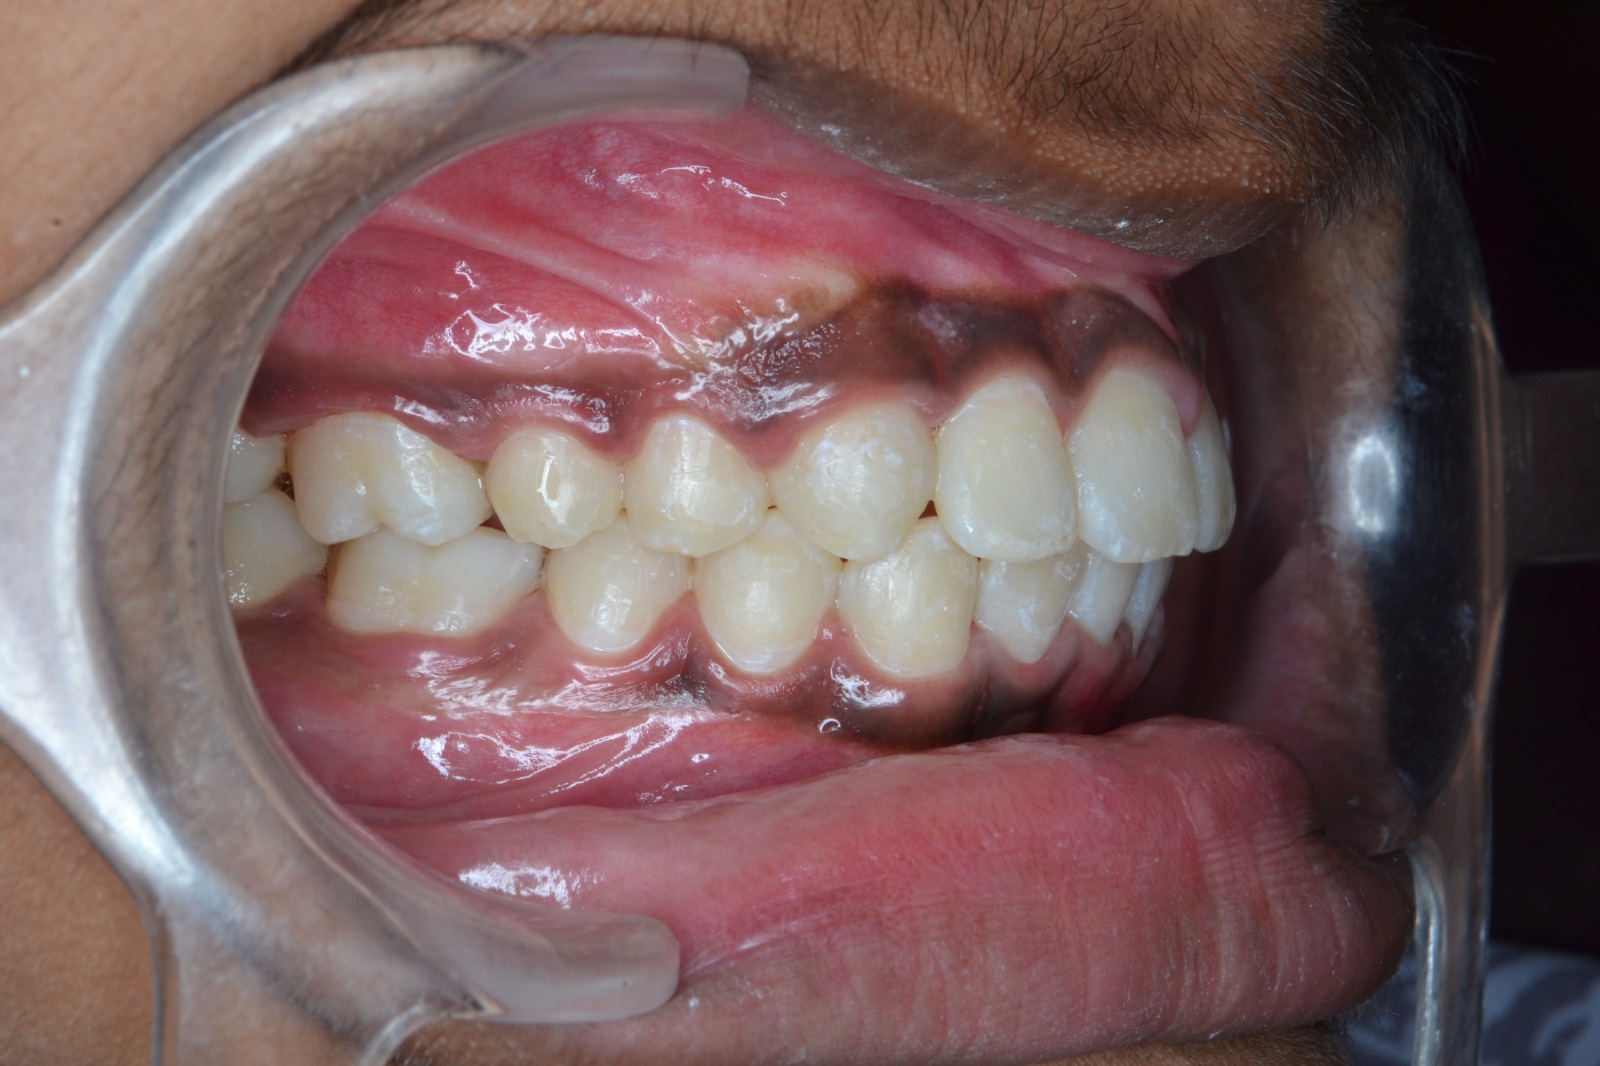

After/Before

See stunning smile transformation before and after